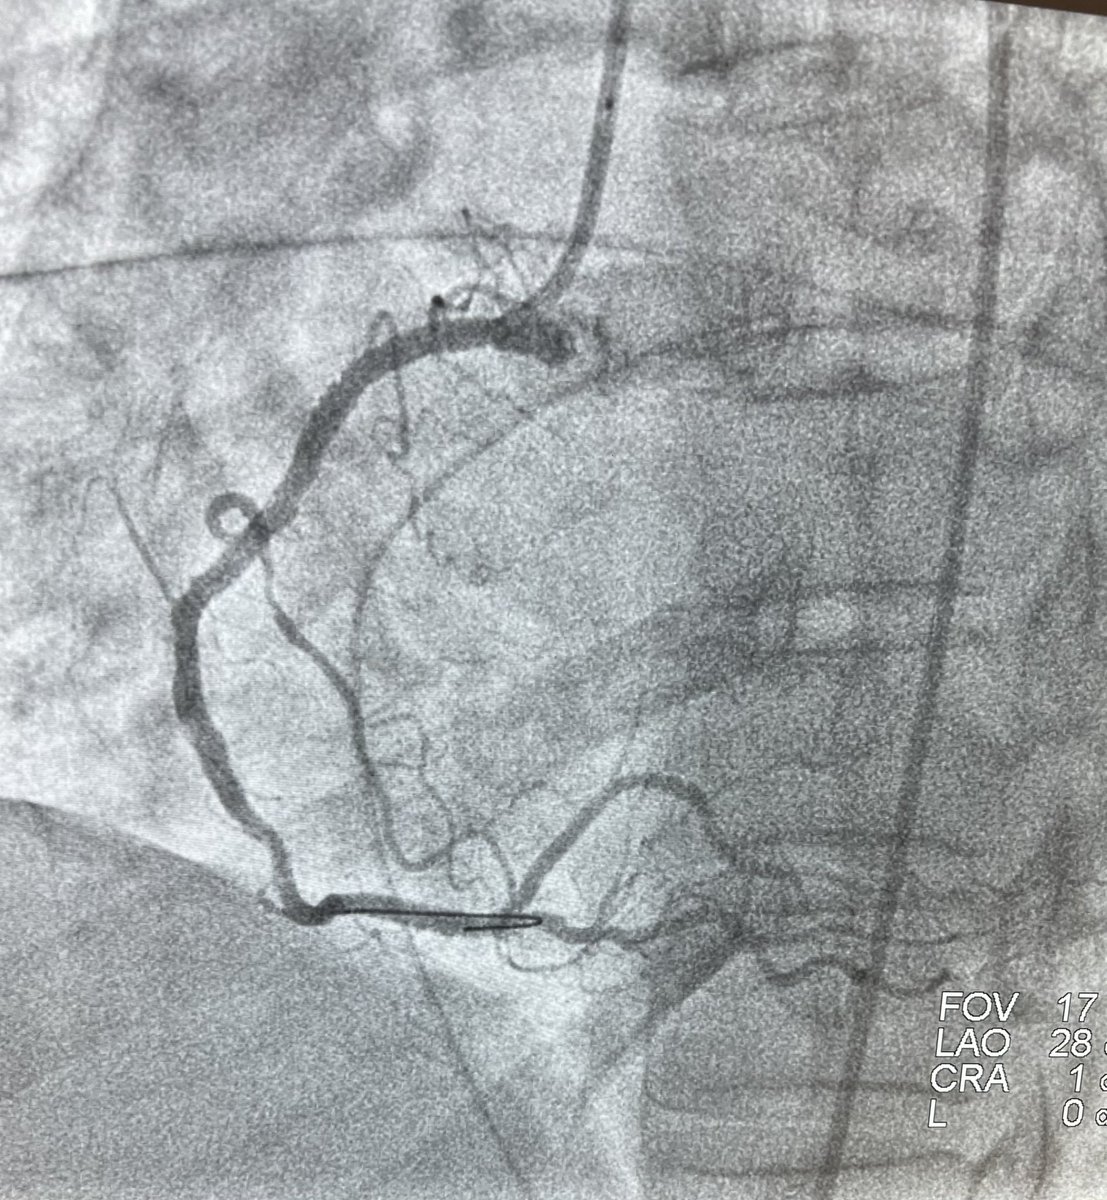

Take a look! The August 2021 Ohio Chapter-ACC #ACCFIT Research of the Month highlights research from Akash Goyal It is entitled Clinical and Economic Implications of Inconclusive Noninvasive Test Results in Patients with Suspected Coronary Artery Disease. ow.ly/P9HA50FnUvK